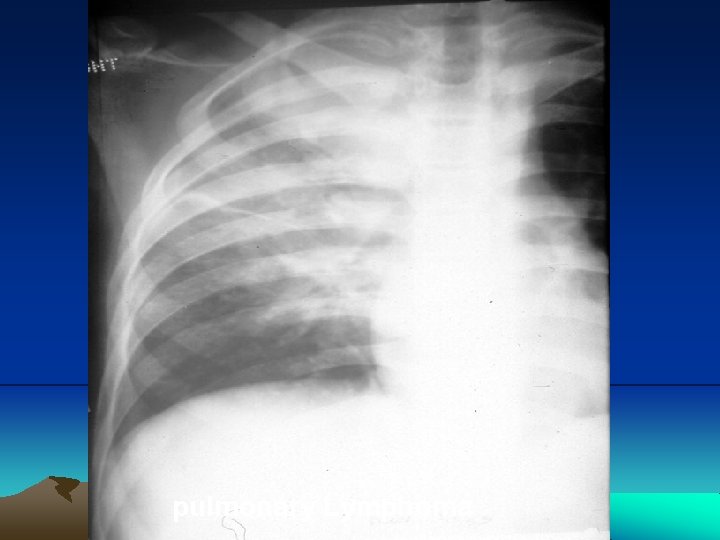

Mediastinal Lymphoma

Mediastinal Lymphoma